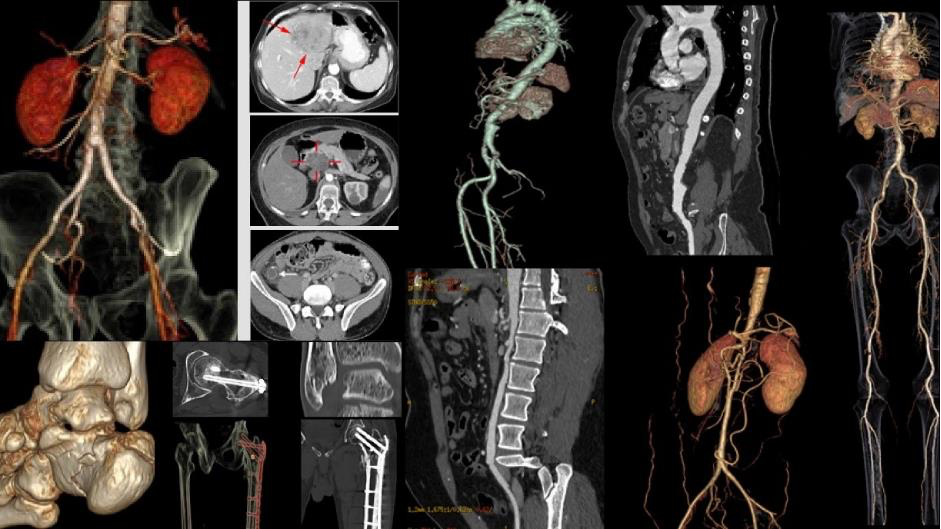

2 nghiên cứu từ Bernard được đánh giá cao tại Hội nghị Ningen Dock Nhật Bản- Ảnh 1.

Hình ảnh học CT Scan tái hiện rõ nét các chi tiết bên trong cơ thể, giúp bác sĩ phát hiện sớm những tổn thương và nguy cơ bệnh lý tiềm ẩn

Bernard Healthcare và các bác sĩ Bernard hiện là thành viên của Hiệp hội Ningen Dock Nhật Bản. Dựa trên hướng dẫn tiêu chuẩn quốc tế, đội ngũ bác sĩ cùng Hội đồng Y khoa Bernard đã xây dựng và nâng cấp gói tầm soát chuyên sâu Ningen Dock Bernard, với đầy đủ trang thiết bị hiện đại như MRI thế hệ mới tích hợp AI, CT Scan, nội soi hiện đại…, đáp ứng tiêu chuẩn của các gói chuyên sâu nhất theo hướng dẫn của Hiệp hội.